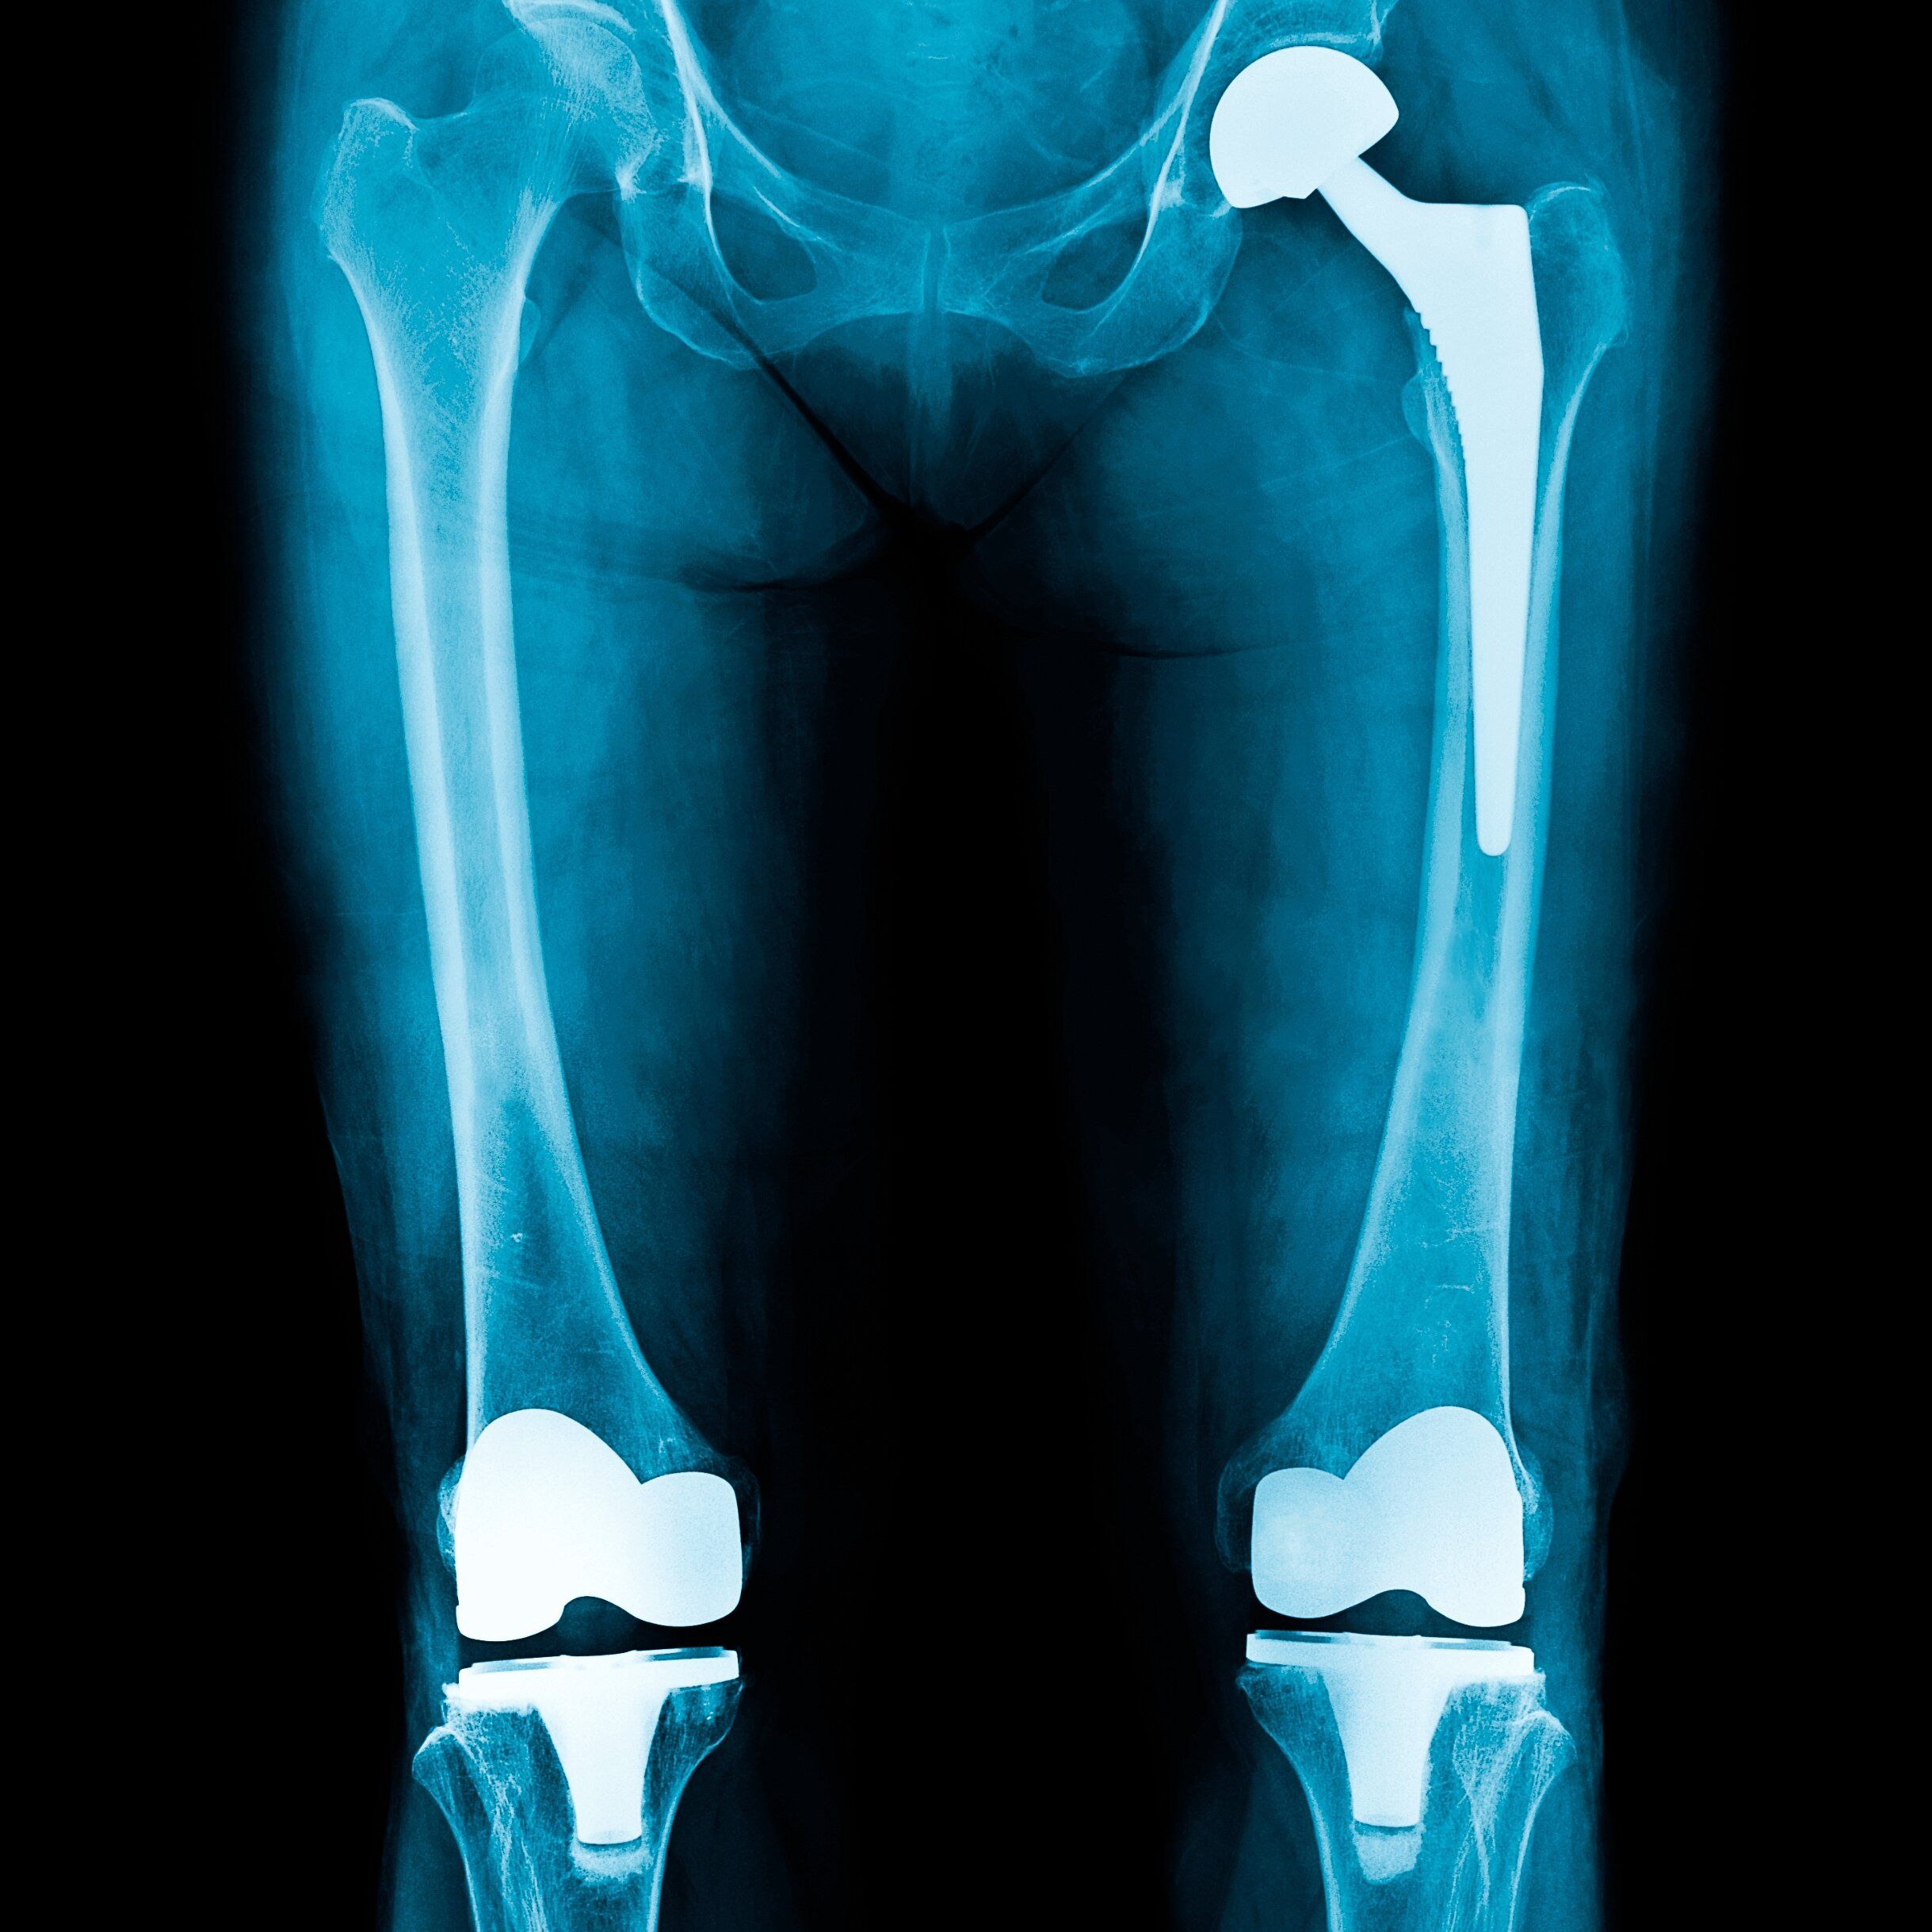

Knie und Hüfte im Fokus

Wenn jede Bewegung schmerzt: Welche Möglichkeiten bietet die moderne Gelenkchirurgie – und wann helfen konservative Therapien? Informativer Abend mit Kombination aus Klinik und Praxis.